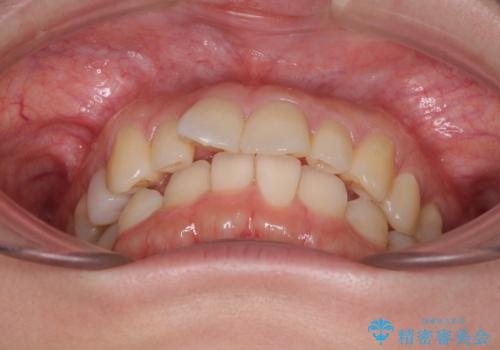

- 上顎前歯の突出感を気にして来院された患者様です。

下顎前歯2本が先天欠損しており、上顎歯列に対して、下顎歯列がアンバランスに小さい状況でした。

左右上顎側切歯2本が矮小歯であるため、上顎の抜歯ではなく、IPR(歯と歯の間を削る)と歯列全体の後方移動によってバランスを整えることとしました。